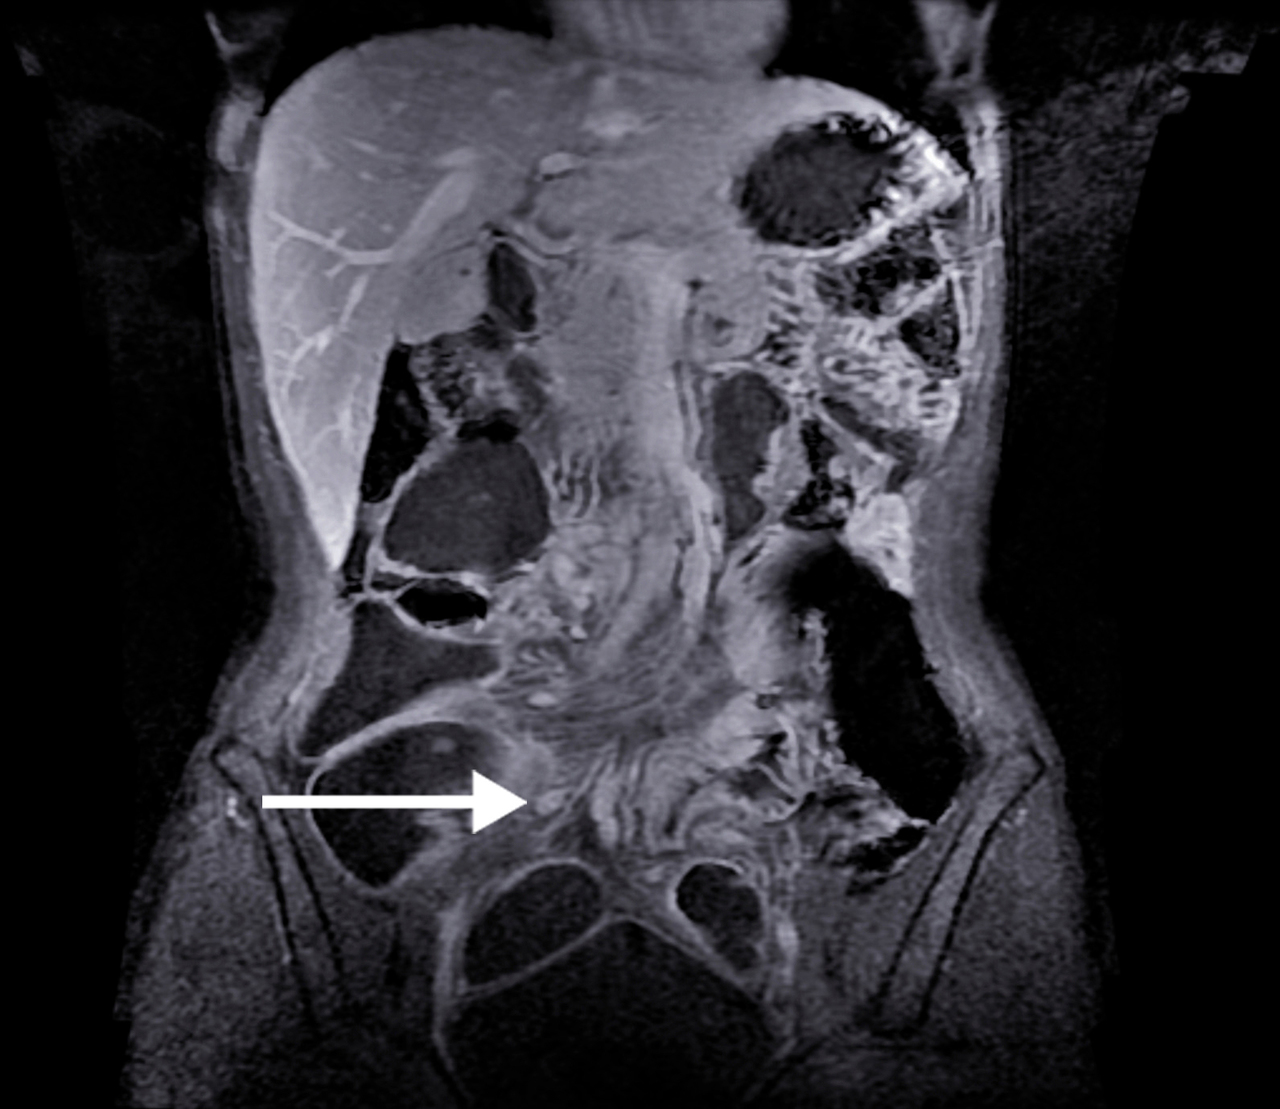

IRM. Adénopathies mésentériques chez une malade ayant une maladie de Crohn de l'iléon.